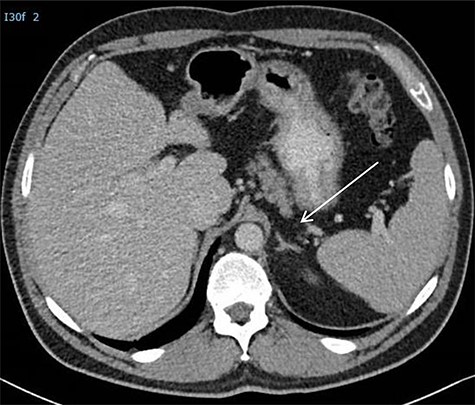

(A) CT scan showing two retroperitoneal masses. (B) CT scan showing retroperitoneal recurrence..

A 26-year-old man was first diagnosed in 2008 with a left-sided testicular tumor treated with inguinal orchiectomy. Resection specimen showed primarily embryonal cell carcinoma and teratoma. The patient, with stage IIC NSTGCT and intermediate-risk group according to International Germ Cell Cancer Collaborative Group [5], received four courses of cisplatin-based chemotherapy. Restaging procedures revealed normalized alpha-fetoprotein (AFP) and a normal beta-human chorionic gonadotropin < 1 U/L. Furthermore, CT scan of the thorax and abdomen showed a left-sided retroperitoneal para-aortic tumor mass, situated caudally of the renal hilus, measuring 6 × 7 cm (prior 5 × 5 cm), and a second retroperitoneal mass situated interaortocaval measuring 1.7 × 1.9 cm (prior 2.6 × 3 cm) (Fig. 2A). Subsequently, the patient underwent a midline laparotomy to resect these tumor masses. Surgical specimens consisted of R0 resection with fibrotic tissue and teratoma with mature and immature compounds. Due to a lack of patient adherence, follow-up protocol could not be executed.

He presented himself 6 years later with a request to resume follow-up, in the absence of symptoms. A retroperitoneal recurrence located at the left retrocrural space with a diameter of 17 mm (Fig. 2B) with normal tumor markers was diagnosed 87 months after initial resection of RRTM. The recurrence, suggestive for a growing teratoma, was located far from the previous operative resection area. The patient was discussed in the multidisciplinary tumor board and offered a posterior retroperitoneoscopic resection of the recurrent disease with the highest chance of a complete resection of this late relapse without surgically dealing with scarred tissues and adhesions caused by a former operation field.